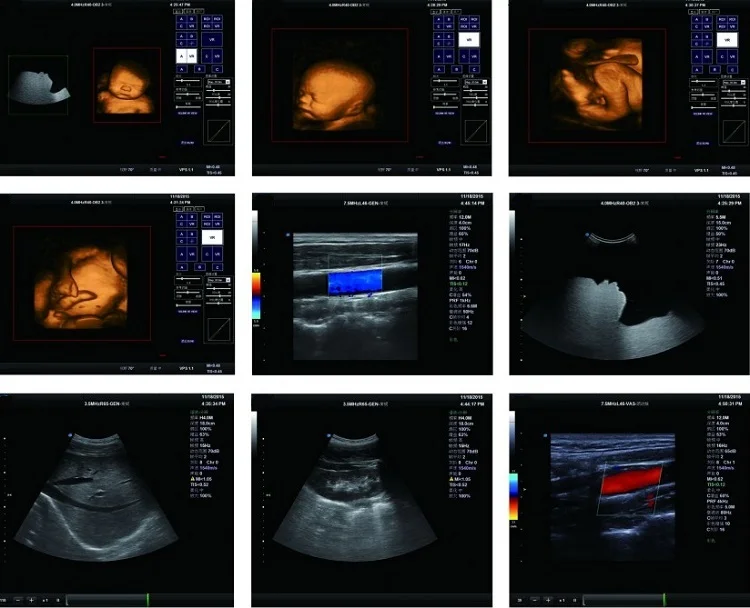

30. របៀបថតរូបភាព 3D ពិតប្រាកដ: ឧបករណ៍ដែលបានបំពាក់ដោយកញ្ចប់កម្មវិធីម៉ូឌុលម៉ូឌុលដែលបានបង្កើតឡើងក្នុងរយៈពេល 4D (3D) អ្នកប្រើអាចប្រើ 3D 3D ស៊ើបអង្កេតដែលត្រូវគ្នាដើម្បីទទួលបានមុខងារល្អឥតខ្ចោះនៃរូបភាព 4D ។

31. ពហុកញ្ចប់បន្ថែមលើកញ្ចប់កម្មវិធីវាស់ទូទៅរោគស្ត្រីរោគស្ត្រីនិងសម្ភពបេះដូងអ្នកជំនាញខាងការវះកាត់ឆ្អឹងនិងការវិភាគលំហូរឈាមពិសេសបានបំពេញតំរូវការ គ្លីនិកនេះ។

38. ជាមួយនឹងការស៊ើបអង្កេតកម្រិតសំឡេង 3D (4D) ពេលវេលា: 2,0-5.5 MHz, ប្រេកង់ 4 ប្រភេទដែលអាចលៃតម្រូវបាន។